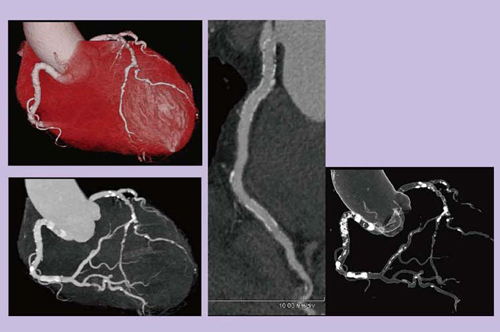

図5は,冠動脈バイパス術(CABG)で,グラフトを4本使用している症例のフォローアップであるが,アーチファクトもなく,十分評価可能な画像が得られている。

図5 78歳,男性,CABGフォローアップ